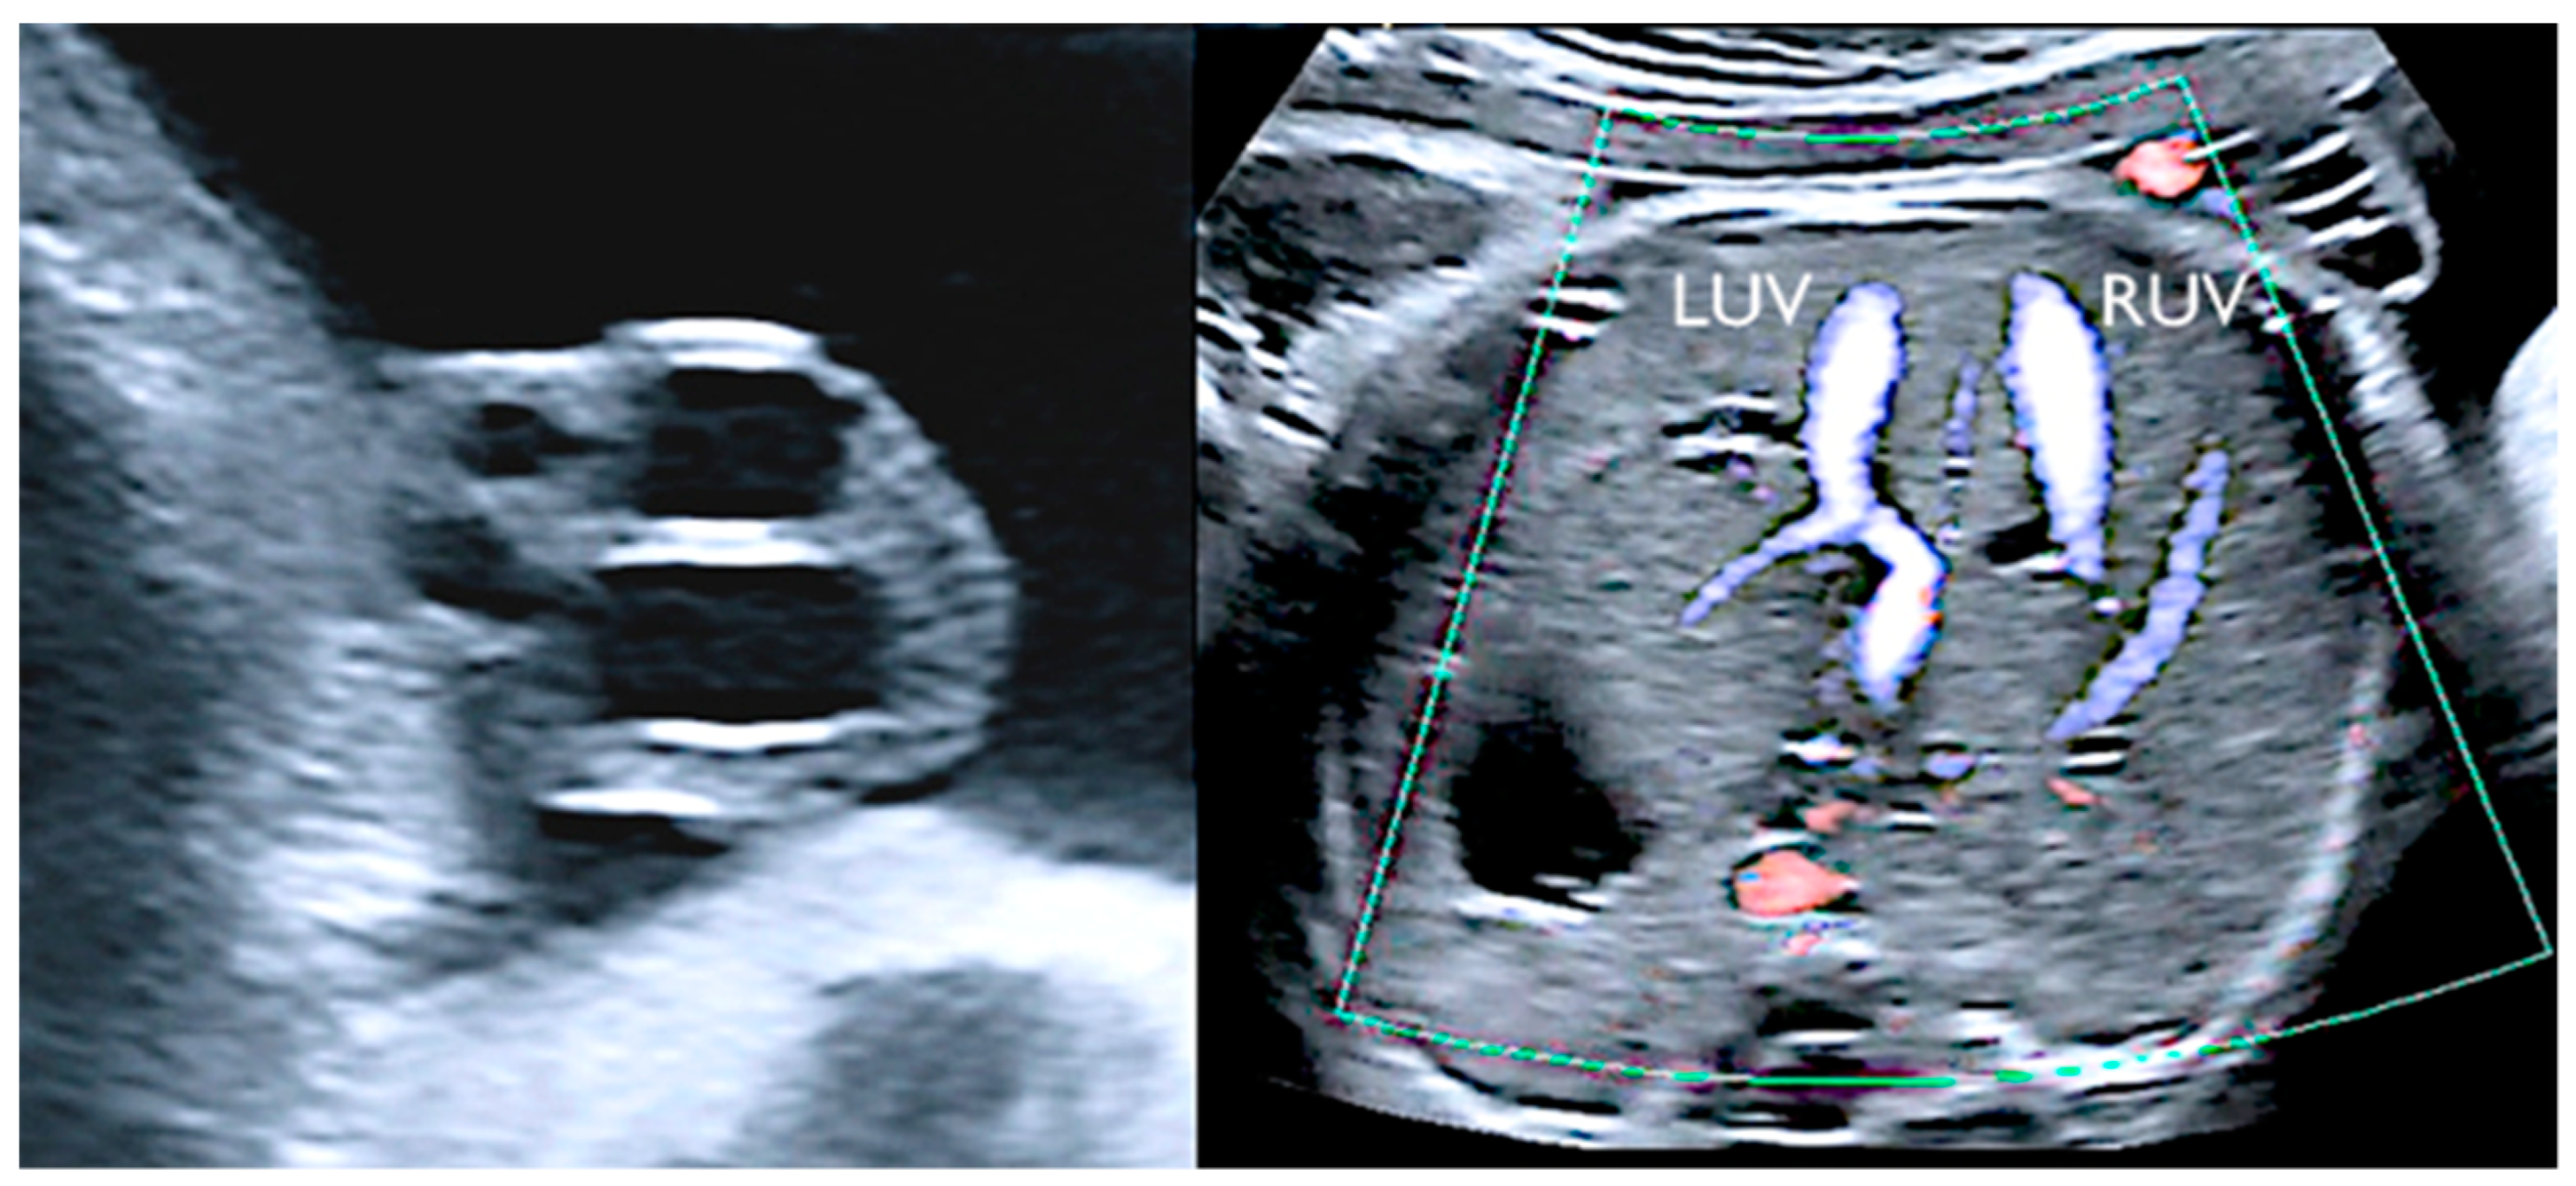

3.5. Supernumerary Vessels